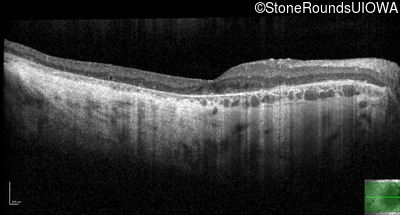

Optical Coherence Tomography - Right - 20/200

Exemplar / OCT Stack